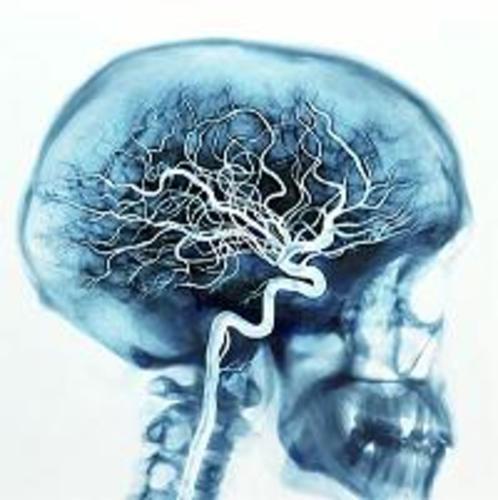

1. Su funcion primordial es la de captar y procesar rapidamente las señales ejerciendo control y cordinacion sobre los demas organos para lograr una adecuada interaccion con el medio ambiente cambiante.

1. el sistema nervioso central esta conformado por el encefalo y la medula espinal,el encefalo lo constituyen el cerebro, el cerebelo yel tallo cerebral.el sistema nervioso periferico lo integran diferentes nervios perifericos que emergen o llegan a la medula espinal.